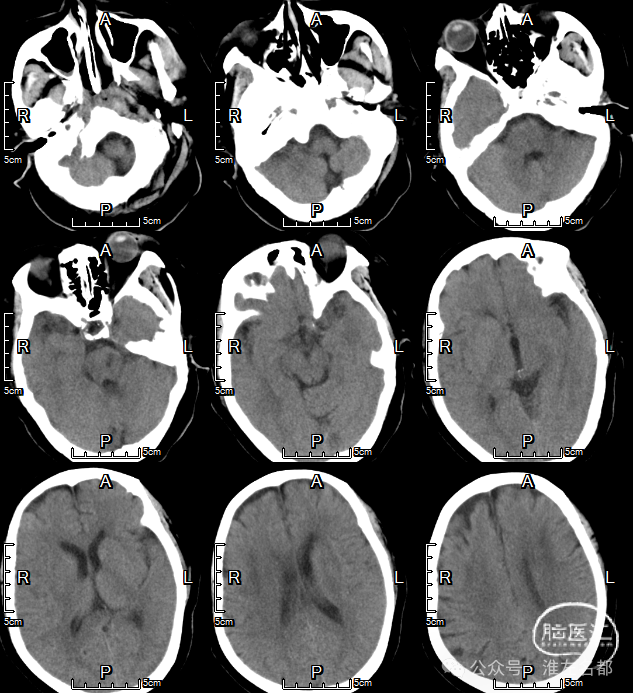

急诊多模式CT

颅脑CT平扫:脑白质改变,余未及其他明确异常。

CTA:基底动脉闭塞,双侧胚胎型后交通,基底动脉尖部可见造影剂充盈;弓上血管迂曲明显,双侧椎动脉V1段均见明显曲折,左侧椎动脉颅内段显影不清,但可见右侧椎动脉颅内段延续至基底动脉闭塞近端。

CTP:脑干和小脑广泛TTP延长,但未见明显CBV和CBF严重降低区域。

术后1个月复查的颅脑CT

CT平扫:左脑桥见一小片状低密度梗死灶。